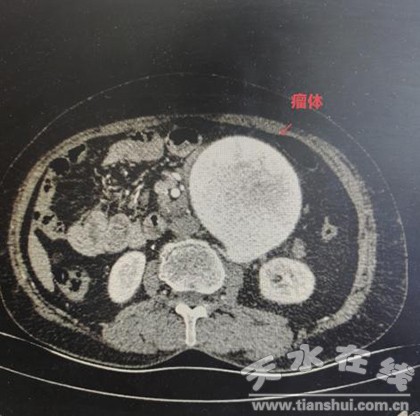

近日,市一院心血管外科收治了一位患有巨大腹主動脈瘤的79歲患者。經(jīng)相關(guān)檢查,主動脈CTA檢查證實患者為腹主動脈瘤,瘤體大小約9.8cm×8.5cm;腹部超聲提示肝囊腫、雙腎囊腫;心電圖提示頻發(fā)室性早搏;心臟超聲示心功能不全;颊呒韧新璺、睡眠呼吸暫停、冠心病等病史。患者隨后被轉(zhuǎn)送到心血管外科重癥監(jiān)護(hù)室,控制心律失常、改善心肺功能、維持生命體征穩(wěn)定,心血管外科團(tuán)隊立即投入緊張的救治。瘤體直徑接近10cm的腹主動脈瘤在臨床上實屬少見,這顆人體內(nèi)的“不定時炸彈”隨時可能發(fā)生破裂而致患者突然死亡,且患者已出現(xiàn)先兆破裂的征象,只有盡快實施手術(shù)治療,才有可能挽救患者生命。

(主動脈CTA中的瘤體)